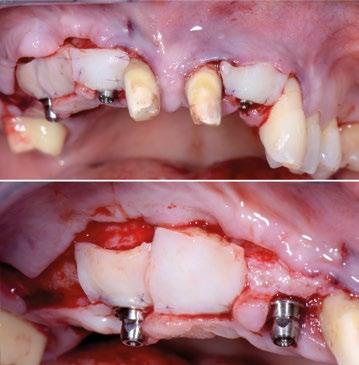

La paciente, de 47 años, se presenta a nuestra observación con una situación gravemente comprometida en varios frentes. La enfermedad periodontal ha causado importantes déficits en los tejidos duros y blandos, recesiones en toda la arcada superior y la pérdida de los elementos dentales del 13 al 15, asociada también a lesiones cariosas destructivas difusas.

Se lleva a cabo la eliminación de los elementos más comprometidos e irrecuperables, permitiendo que los tejidos se curen durante 6 meses, durante los cuales se coloca una prótesis provisional reforzada en toda la arcada, anclada en los elementos residuales 17, 11 y 21, extendiendo el puente también a los elementos 23,

24 y 25 con alitas tipo Maryland para obtener una adecuada estabilidad manteniendo intactos estos elementos.

Se planea la rehabilitación definitiva con soporte implantario con la ayuda de cirugía guiada e implantes Prama Short Neck. En las posiciones 12 y 22 se colocan implantes de 3,80 mm de diámetro y 11,5 mm de altura, mientras que en la posición 15 se planea la colocación de un implante de 10 mm de altura inclinado mesialmente para evitar el seno maxilar.

En el momento de la intervención, se realiza un colgajo de espesor total y se extiende apicalmente a espesor parcial: esto, por un lado, evitará la interferencia del grosor de los tejidos blandos con la máscara; por otro lado, es precursor del injerto de tejido conectivo tomado del paladar del paciente que reconstruirá los volúmenes de los tejidos duros y blandos que faltan, la parte supraósea de la raíz, previamente perdida.

Fotos iniciales que muestran claramente el grave compromiso de la arcada superior debido a la enfermedad periodontal. Giovanni Zucchelli Alessandro Zucchelli Pietro Bellone

Radiografías intraorales iniciales.

Radiografías a los 6 meses de curación.

Tejidos a los 6 meses de curación.

Curación después de la limpieza con provisional reforzado anclado en los elementos residuales 17, 15, 11, 21, 23, 24, 25.

Fase quirúrgica: apertura del colgajo.